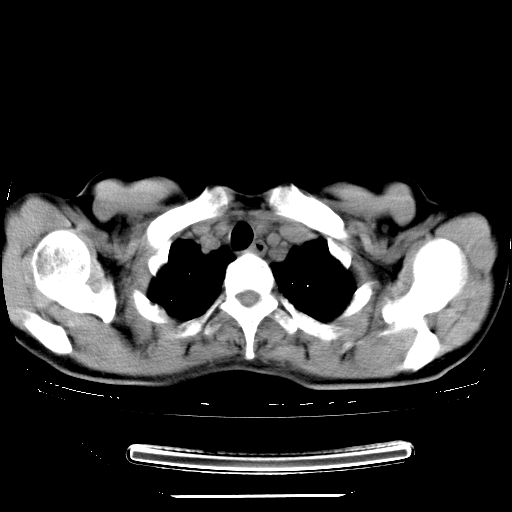

标题: CT27224:女,43岁,体检发现左肺下叶结节影。 [打印本页]

女,43岁,体检发现左肺下叶结节影。

左下肺外带胸膜下见孤立实性均匀密度结节影,边缘光整,增强呈渐进性强化,病灶吴分叶征及毛刺征象;支持硬化性血管瘤。

左肺下叶基底段圆形结节,多考虑:错构瘤>硬化性血瘤>炎症假瘤>周围性肺癌!期待结果!

左肺下叶外侧基底段圆形结节,多考虑:错构瘤>硬化性血瘤>炎症假瘤>周围性肺癌!期待结果!

良性结节,有钙化,强化不明显,考虑软骨性错构瘤。

左肺下叶外基底段良性结节(错构瘤?)。